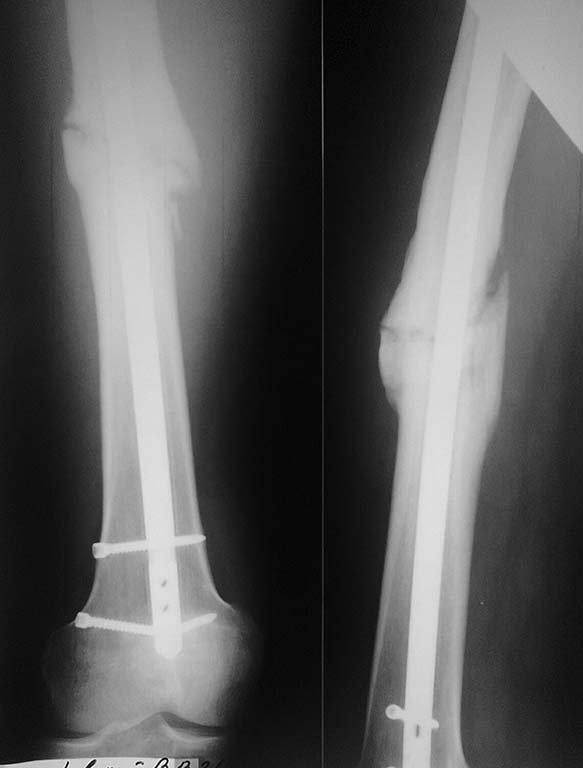

Хотели установить максимально толстый штифт и блокировать динамически. Послеоперационные снимки прилагаются.

Универсальный гвоздь ChM или DC-"Деост". Возможно введение антеградно/ретроградно. Овальные отверстия на обоих концах гвоздя.

Ждать на стоит. Рассверлить, толстый гвоздь - динамически. Или как Александр Николаевич предлагает. Я б снизу 3 винта ввел в разных плоскостях. "Беда" Деостовских гвоздей - блокирующие винты 4,5 мм.

Клинически- боль в области перелома при длительной нагрузке. Штифт- DC.

Мне кажется, произошла избыточная динамизация в ближайшем послеоперационном периоде, т. е. появилась нестабильность. Скорее всего, дистальный винт - сломался (полнорезьбовой - более склонен к разрушению на изгиб). Считаю достаточным - зафиксировать (заново) дистальный отломок на стержне. Выполнить СТАБИЛЬНЫЙ остеосинтез.

Хотя правильно - более толстый стержень с рассверливанием.